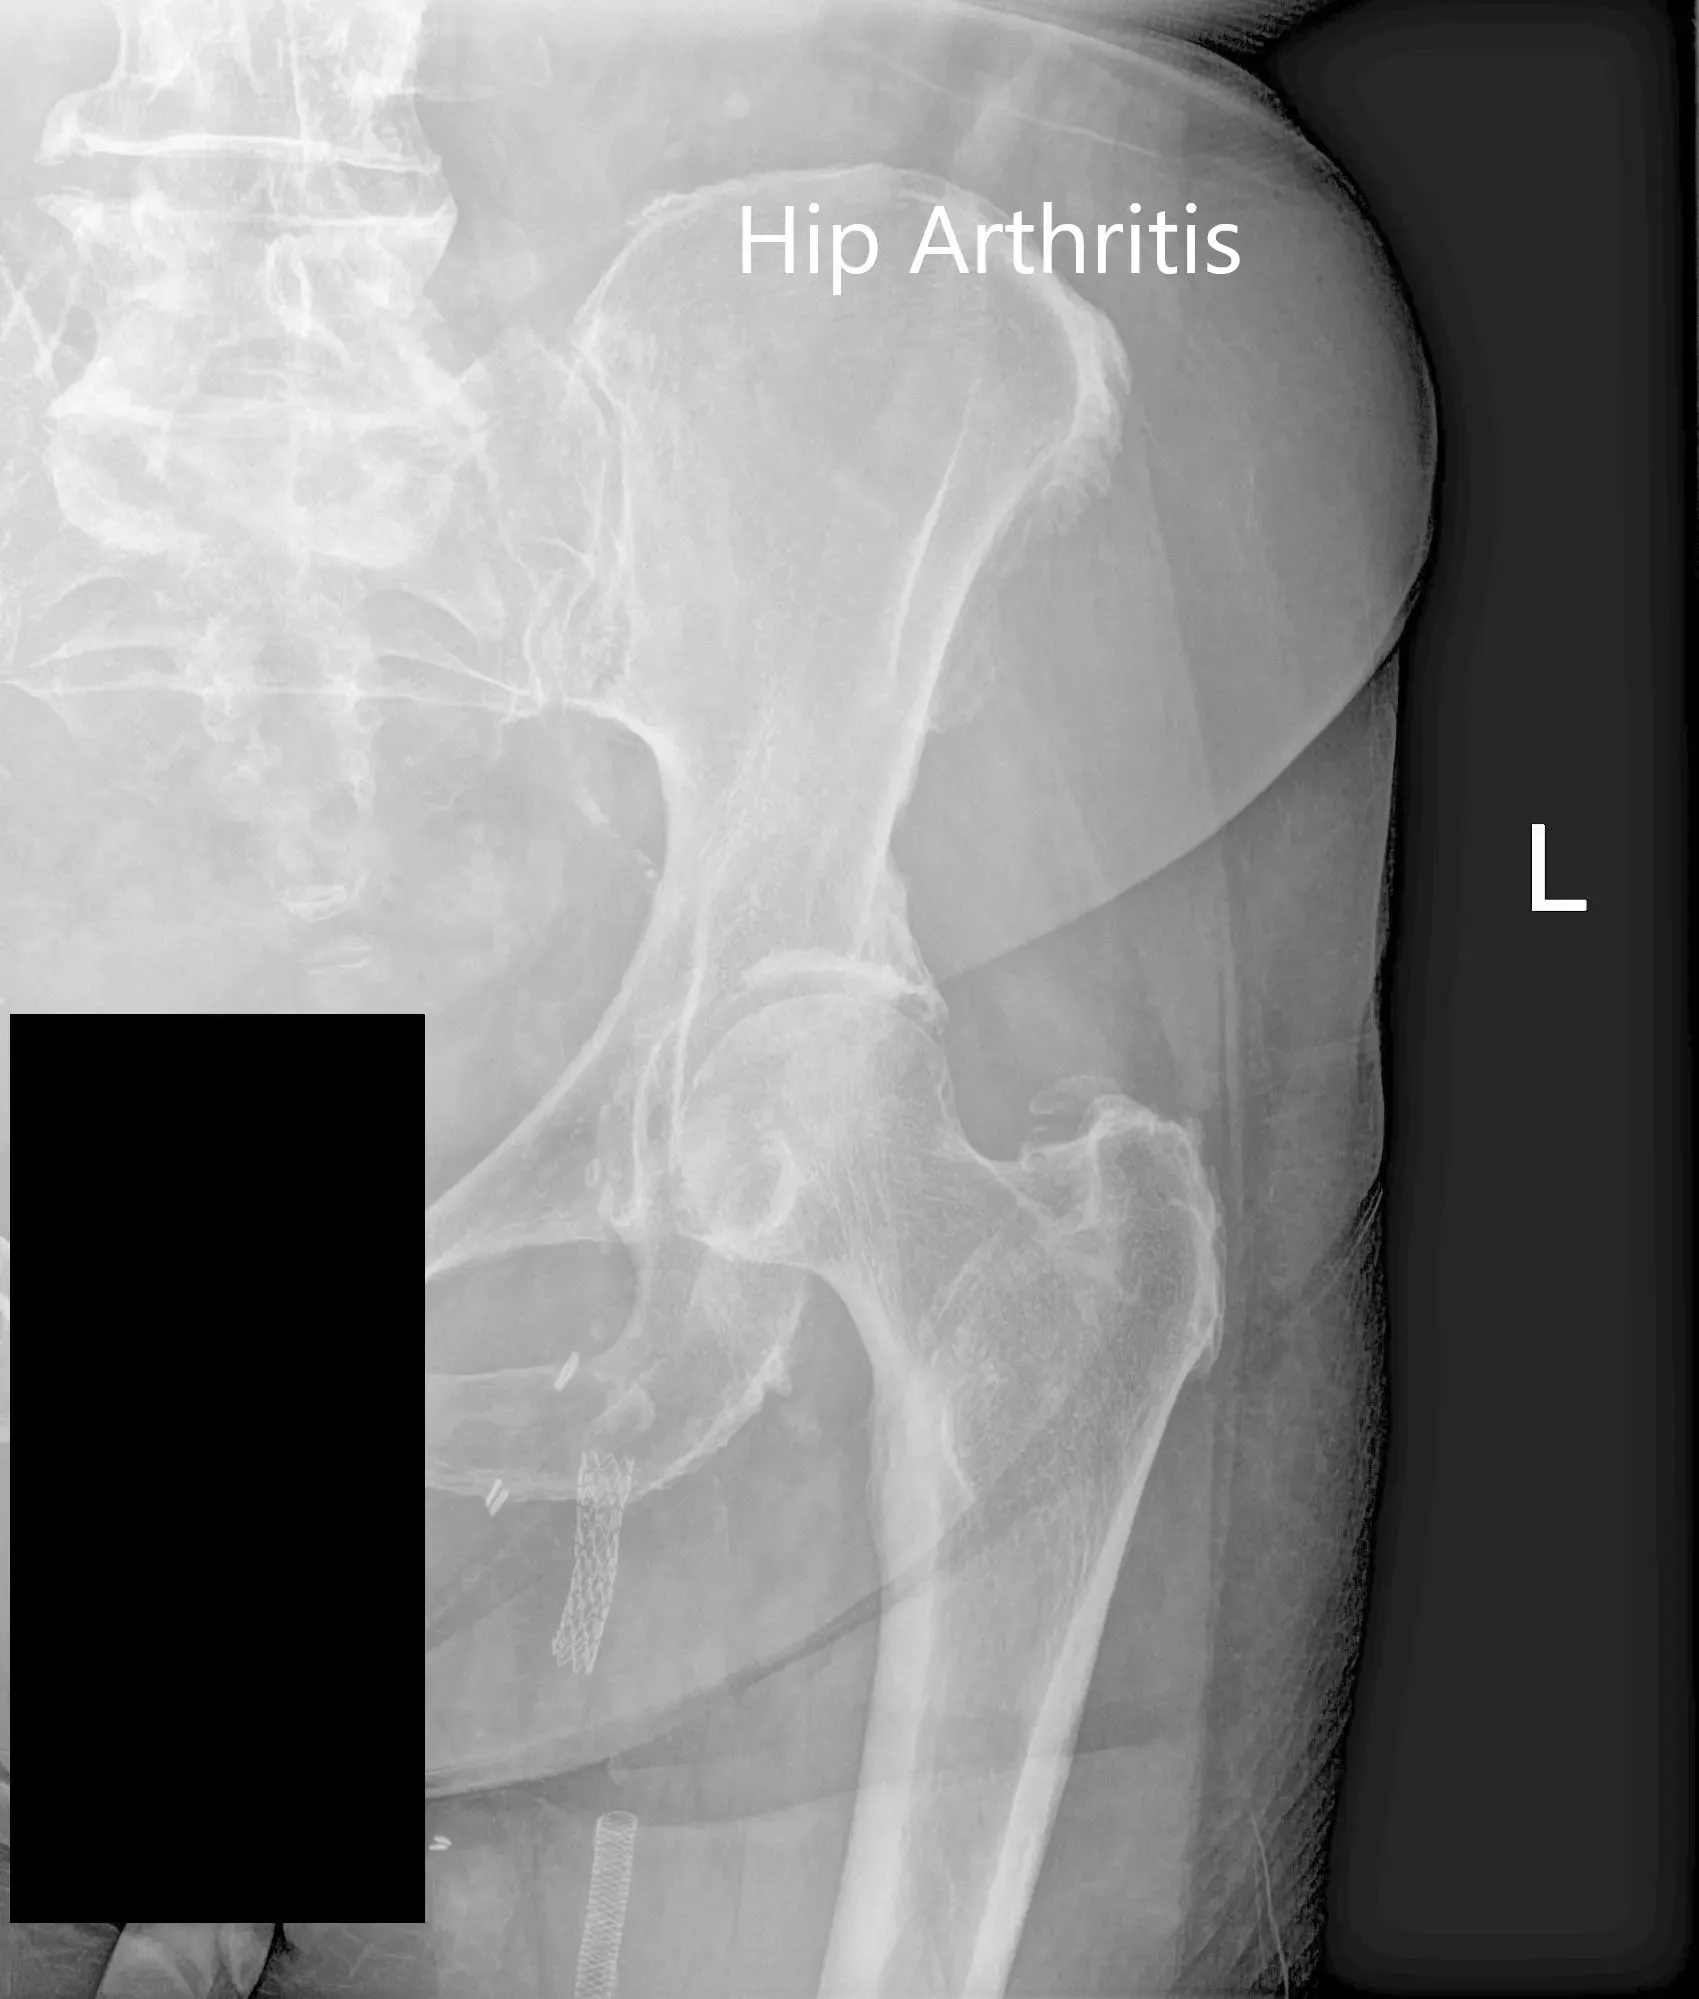

El estudio de imagen reveló artritis bilateral en la articulación de la cadera. Hubo cambios degenerativos severos en la cadera izquierda. Tras considerar cuidadosamente sus factores de riesgo cardíaco, se le recomendó una artroplastia total de cadera izquierda. Se discutieron extensamente con él riesgos, beneficios y alternativas. Aceptó someterse a una prótesis de cadera izquierda.

Radiografía preoperatoria de la cadera izquierda que muestra las vistas laterales de la pata de rana y la perna de rana